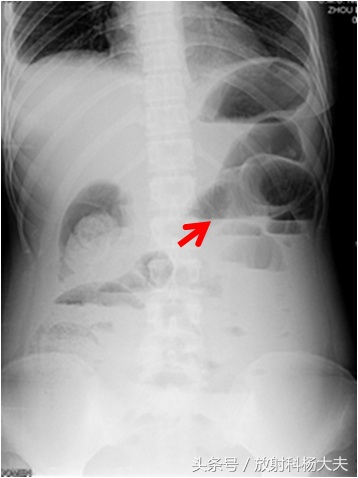

急诊医生一检查,急腹症,先拍片子吧。拍了腹平片,典型的肠梗阻的表现。

红箭所示为肠梗阻导致的气液平面

在X线片上,一般让病人站着拍腹部,如果有明显的梗阻会看到肠道扩张,并出现气液平面,正常的成人小肠内是没有气体的,也不会有气液平面,大肠内可以有少许气体,但肠道不会扩张。